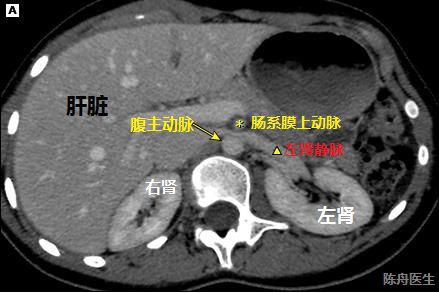

“胡桃夹综合征”(NCS,nutcracker syndrome )又被叫做“左肾静脉压迫综合征”,具体是指左肾静脉(left renal vein,LRV)穿行于肠系膜上动脉(superior mesenteric artery, SMA)与腹主动脉(abdominal artery, AA)之间受到两者到“钳压”,从而导致左肾静脉回流受阻而引起的一系列临床症状,比如说血尿,腰痛等。

具体可见上图,当发生胡桃夹综合征时,我们的左肾静脉犹如核桃,被夹出问题来,比如最突出的就是镜下血尿

,甚至是肉眼血尿。

这是一个14岁女孩的腹部CT图像,可以明显的看到左肾静脉在经过腹主动脉和肠系膜上动脉之间时,明显被压扁了很多,此外,大家有没有注意到左肾是明显比右肾大来一圈(发生肾瘀血了)!